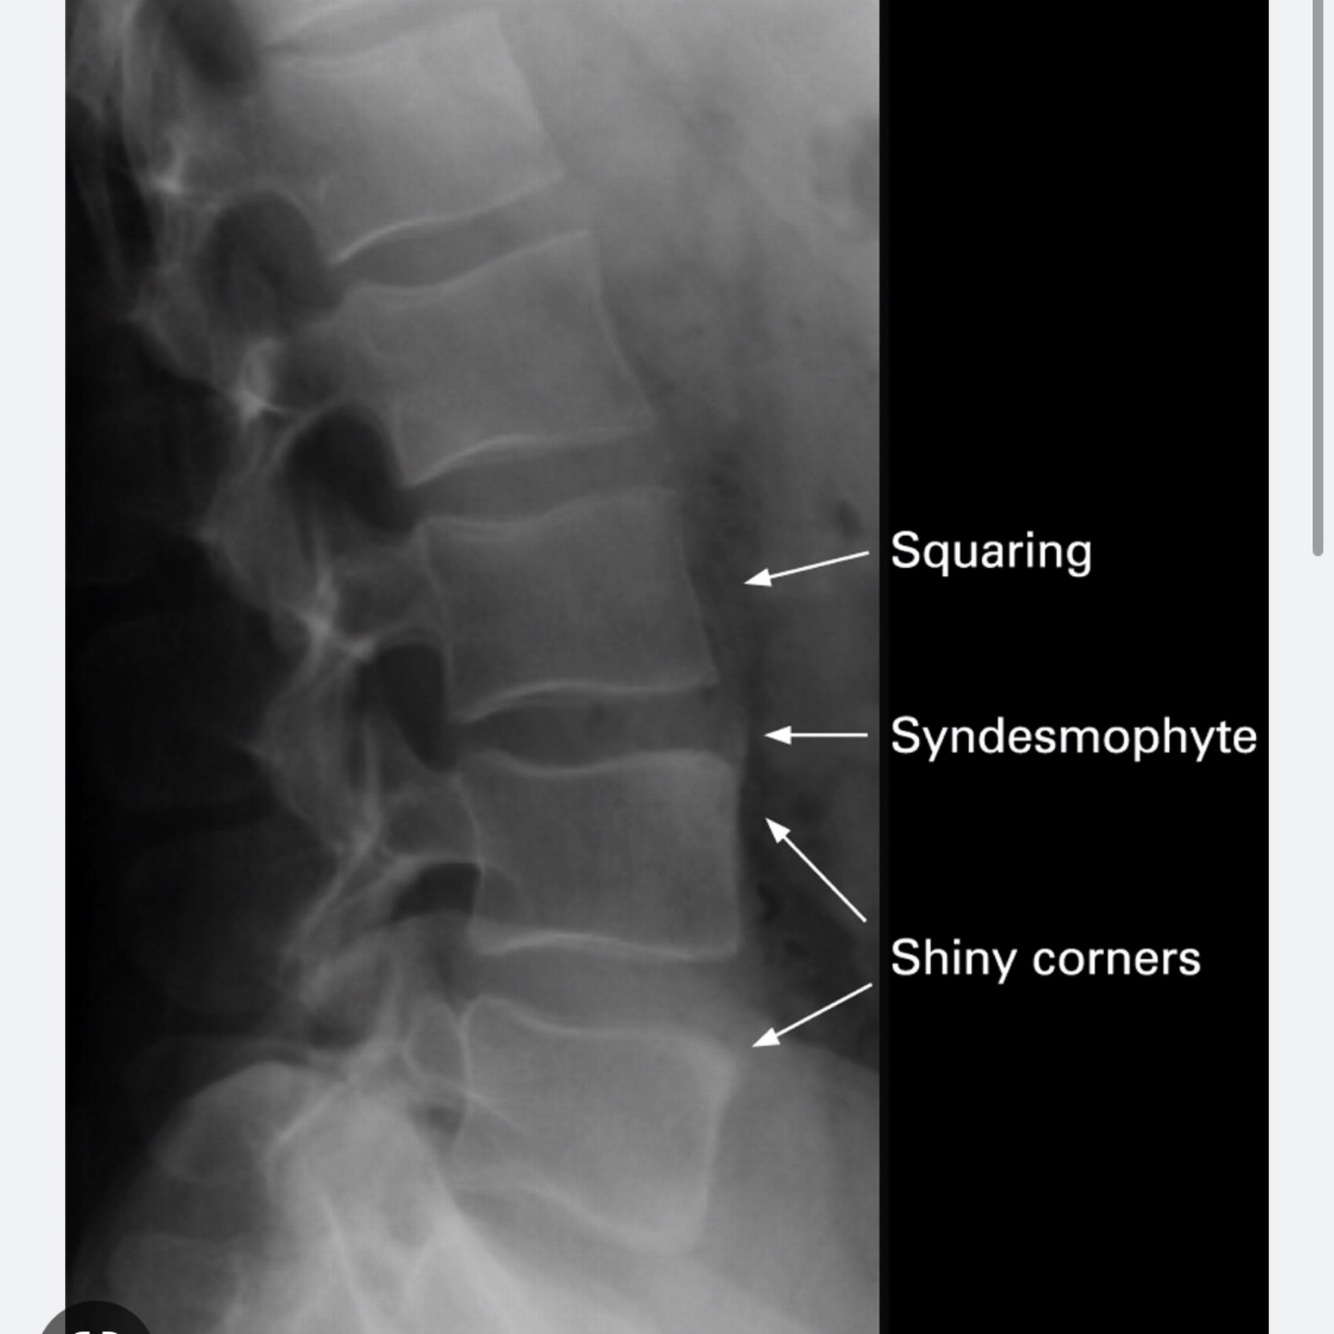

éburnation (shiny corners)

-Shiny corners: The shiny corner sign is a spinal finding in ankylosing spondylitis, representing reactive sclerosis secondary to inflammatory erosions at the superior and inferior endplates

-Aucune idée c’est quoi curvilineaire et ligne noire de L1,

57. Qu’est ce qu’on voit sur radio pour diagnostiquer un Syndrome de Schueurmann? plateaux vertébraux irréguliers ebernuation des corps vertébraux (shiny corner) festonnement antérieur des corps vertébraux (scalloping) trabécules osseux grossiers

plateaux vertébraux irréguliers